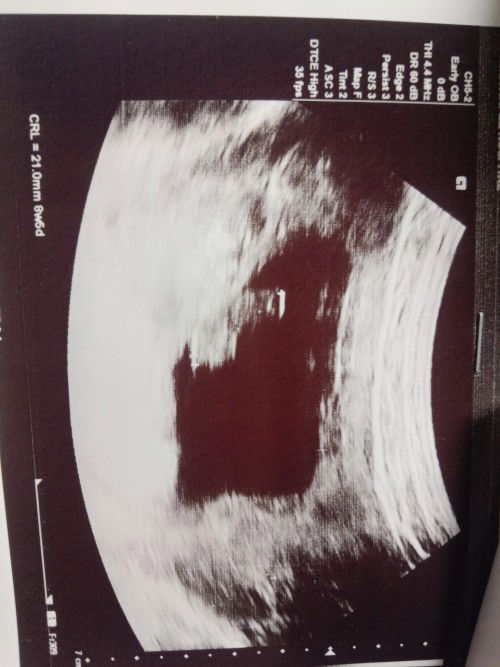

คือปจด.เรามาครั้งสุดท้ายวันที่17ก.พค่ะ เราไปหาหมอไปฝากหมอบอกได้15Wแล้ว แต่พอเราถามในโพสก่อนหน้านี้ว่า เรามีเลือดออกมานิดหน่อยค่ะแต่ไม่ได้ออกแบบเปื้อนกางเกงในเป็นมา2-3วันแล้วค่ะ เราก็ทำตามแม่ๆที่ที่มาเม้นท์ว่าให้ไปหาหมอค่ะแล้วเราได้ซาวด์สรุปคือลูกเราตัวเล็กมากแล้วอายุครรภ์แค่8W +5เองค่ะ ล่ะได้ตรวจช่องคลอดด้วย ปรากฏว่ามีภาวะเสี่ยงแท้งค์คุกคามค่ะแต่เปอร์เซ็นต์แท้งค์มีน้อย อยากทราบจากแม่ๆว่า เราจะหายกังวลได้ไหมคะว่าน้องจะไม่หลุด แนะนำการใช้ชีวิตในช่างเสี่ยงแท้งค์คุกคามหน่อยค่ะ #ขอบคุญสำหรับคำตอบล่วงหน้ามากๆเลยนะคะ